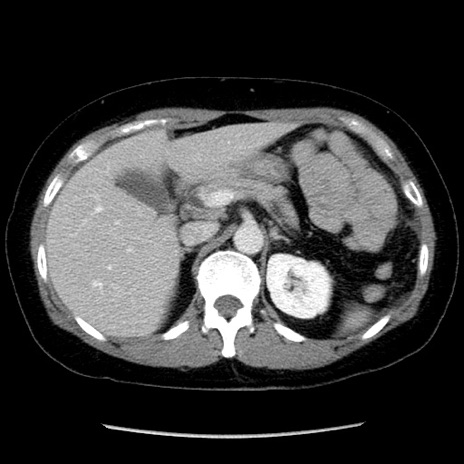

矢状断像

【症例】50歳代女性

【主訴】下腹部痛

【既往歴】卵巣癌術後(8年前に当院で卵巣摘出)

【身体所見】 意識清明、腹部:平坦、腸蠕動音→、やや硬、下腹部自発痛・圧痛あり、反跳痛あり、筋性防御なし。

【データ】WBC 16000、CRP 0.01